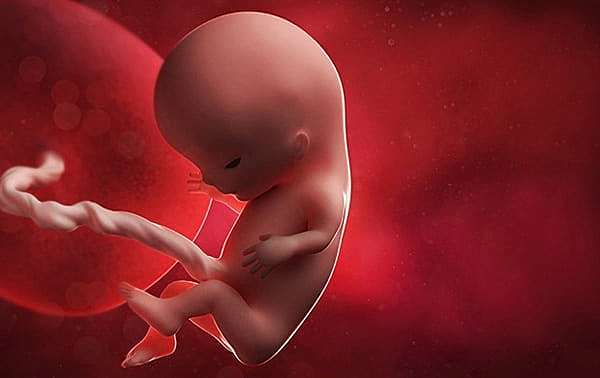

Desarrollo embrionario

Periodo que se produce entre la fecundación y el parto, dura normalmente 9 meses

7

Semana 7

-Los tejidos y los órganos formados en la fase embrionaria maduran.

-La cola del embrión empieza a caer.

-El corazón late y el esqueleto adquiere forma.

-La placenta sigue formándose y empezará a pasar nutrientes del cuerpo de la madre al embrión y retirará sus productos de desecho.

-El cordón umbilical, la línea vital entre madre e hijo, empieza a crecer y ensancharse.